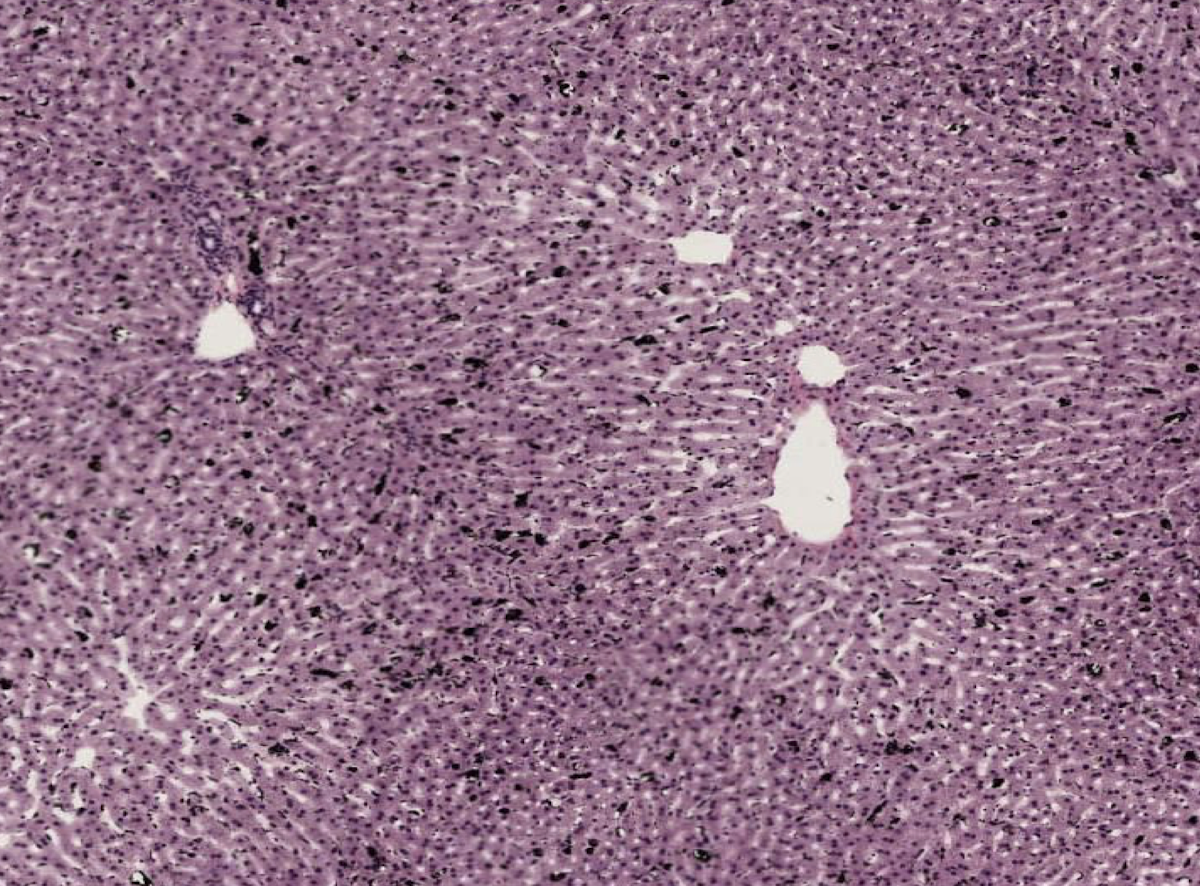

The opposite of stroma is shown here, which is? What are the white looking lines? What cells are shown in the lobule that are very pink?

Parenchyma (main function of organ). What lines are sinusoids (blood vessels) and the cells are hepatocytes (pink).

The perenchyma is made up of what kind of cells? What are within these cells? How are the cells organized?

Epithelial cells called hepatocytes. They contain glycogen granules and are rich in rough endoplasmic reticulum. They are organized into functional units called lobules.

What makes up the portal triads? Classify the tissue of one, and the source of the other two.

Bile duct (cuboidal epithelium), venule (from hepatic portal vein), and arteriole (from hepatic artery)

How can the portal triad be identified histologically?

Vein is large with thin walls. Artery is smaller but muscular, and duct is cuboidal epithelium.